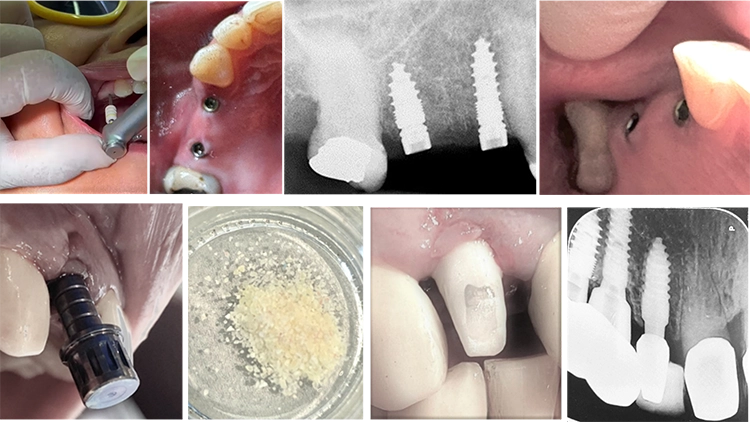

Unter dem Motto „Immer einen Schritt voraus!“ bietet die Future Dental Academy 2-tägige zahnärztliche Wochenendfortbildungen der besonderen Art. Denn hier führen die Teilnehmenden jede Implantation selbständig durch – angefangen von örtlichen Infiltrationsanästhesien bis hin zur Aufbereitung und dem Einsatz. Die Supervisionäre Dr. Armin Nedjat und ZA Gerhard Quasigroch assistieren dabei. Ob Spät- oder Sofortimplantate, die Distraktion schmaler Kieferkämme ohne Lappenbildungen oder interne, direkte Sinuslift-Operationen mit anschließender Implantation: Die Teilnehmenden arbeiten an ganz alltäglichen Patient/-innen. Zudem kommt die Prothetik mit geschlossener Abformung bzw. Scanabformung und der passiven Eröffnung der Gingiva über den Shuttle bei den Kursen nicht zu kurz. Angewandt wird das MIMI-Verfahren, eine minimalinvasive Implantationsmethodik, die 2013 den „Best Innovation in Medicine Award“ (SENSUS) in Dubai gewann und 2017 in Berlin für den „German Medical Award“ nominiert wurde.

Es steht für ein sanftes, fast unblutiges Vorgehen ohne Lappenbildungen, das durch den speziellen Workflow in nur einem Drittel der Zeit einer üblichen Einzelzahn-Implantationsgesamtbehandlung durchführbar ist. Manche der partizipierenden Zahnärztinnen und Zahnärzte setzt bei den praktischen Kursen erstmals ein Implantat, andere nutzen erstmals das MIMI-Verfahren. Bei den Fortbildungen selbst begeistert das Betreuungsteam von Champions und der Future Dental Academy mit seiner freundlichen, offenen Art. Die Teilnehmenden profitieren von der 30-jährigen Erfahrung von Dr. Armin Nedjat und ZA Gerhard Quasigroch, die gemeinsam rund 40.000 Implantatinsertionen und ZE-Versorgungen im MIMI Verfahren vorgenommen haben. Nicht zuletzt stellen die Fortbildungen auch ein gutes Networking-Event dar – und jeder Freitag endet mit einem kollegialen Austausch bei einem Barbecue-Buffet und rheinhessischem Wein.

– eigenständige Aufbereitung der Kavitäten und Implantation – Sofortimplantation u.a. mit WS-Condensern und dem Smart Grinder (autologes Zahnmaterial als KEM) – interner, direkter Sinuslift (IDS: MIMI-6), schmerz-, schnitt- und blutungsfrei in 5 Minuten – Implantation in schmalen Kiefern: MIMI-2 – „ossäre Metamorphose“ von D4- in D2-Knochen durch WS-Condenser in 5 Minuten – alle Kniffe und Tricks des MIMI-Verfahrens |